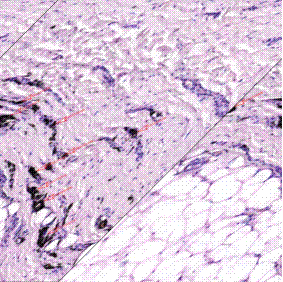

Полученные результаты представлены отдельно для рубцов, имеющих признаки посттравматической импрегнации, и для рубцов, свободных от пигмента. Также в ходе исследования производились замеры указанных показателей в интактной дерме (рис.1 и 2).

Рис.1. Измерение глубины слоя дермы рубца до проведения лазерной терапии. Окраска: гематоксилин + эозин. Ув. х5.

Примечание: составлен авторами по результатам данного исследования

Рис.2. Измерение глубины слоя дермы рубца после проведения лазерной терапии

Окраска: гематоксилин + эозин. Ув. х5.

Полученные данные продемонстрировали стойкую тенденцию к уменьшению толщины дермы на препаратах посттравматических рубцов с элементами импрегнации (табл.1) [13]. Так, в паре препаратов №1 при сравнении выявилось снижение толщины дермы на 28,84%, что явилось статистически значимым изменением (p=0,005). Схожая картина наблюдалась в паре №3: регресс толщины дермы составил 30,4% (p=0,005). В паре №2, несмотря на тенденцию к снижению толщины дермы, статистически значимых различий получено не было (p=0,074).